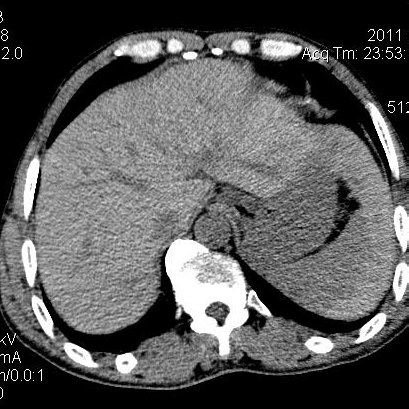

肝左叶发育异常

男性,55岁,骑摩托车摔倒后入院,自述右上腹疼痛

[backcolor=#FF0000]第一次诊断的时候也是这么肯定,可是床旁超声检查并没有发现明显异常,而且患者的一般症状都良好。还好临床只是保守治疗,没有立即手术,第二次复查的时候没有一点变化,又做了MRI检查,没有血肿,

这是一例肝左叶发育异常的,很个性吧~[/backcolor]